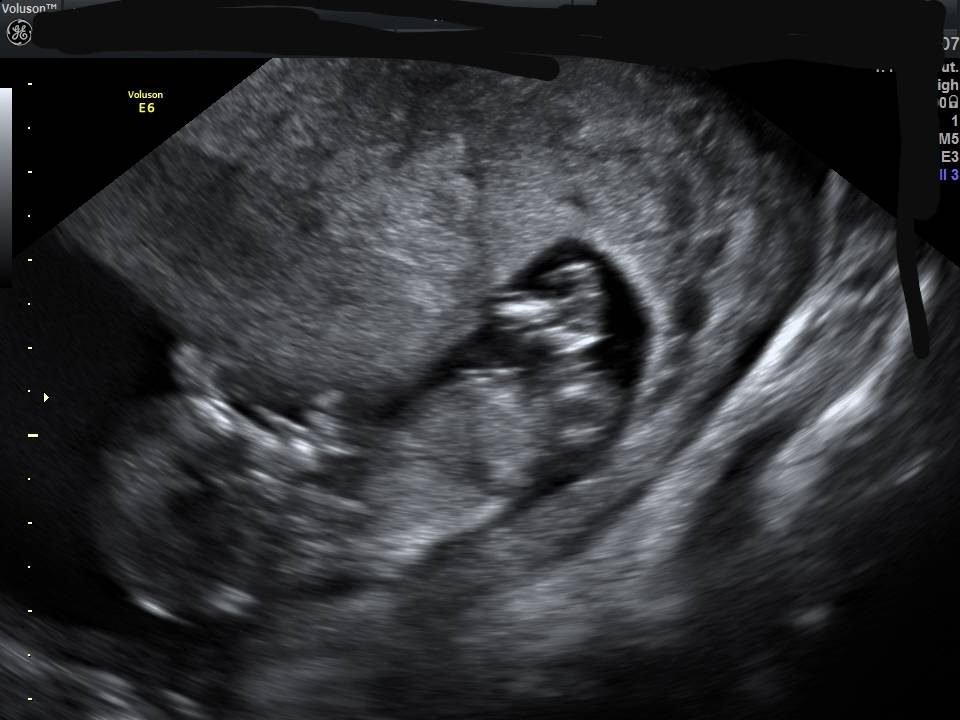

Kochane to moja dzidzia niestety na zdjeciu ktore wyslalam na grupe fb nie widza. Myslicie ze zdjecie nr 2 jest lepsze?